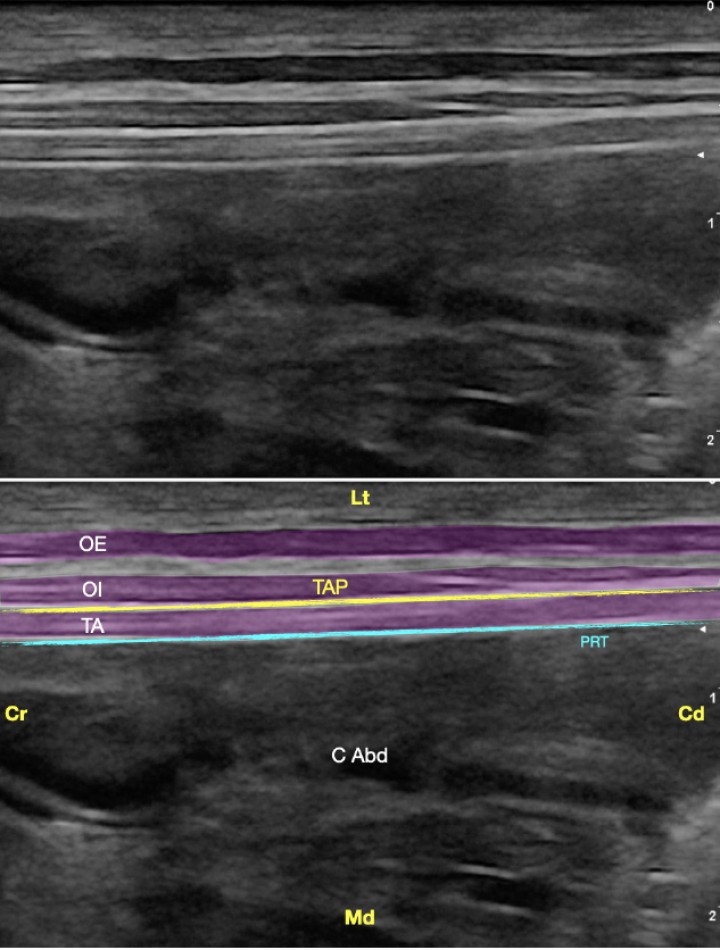

<p>Imagen ecográfica del plano transverso abdominal lateral. Músculo oblicuo externo (OE), músculo oblicuo interno (OI), músculo transverso abdominal (TA), plano del transverso abdominal (TAP), peritoneo (PRT), cavidad abdominal (C Abd). Cr: Craneal, Cd: Caudal, Lt: Lateral, Md: Medial.</p>

Figura 11

Imagen ecográfica del plano transverso abdominal lateral. Músculo oblicuo externo (OE), músculo oblicuo interno (OI), músculo transverso abdominal (TA), plano del transverso abdominal (TAP), peritoneo (PRT), cavidad abdominal (C Abd). Cr: Craneal, Cd: Caudal, Lt: Lateral, Md: Medial.

<p>(<strong>A</strong>) Posición del transductor y la aguja para el abordaje en plano del plano del transverso abdominal lateral. (<strong>B</strong>) Imagen esquemática de las estructuras anatómicas y la aguja. Músculo oblicuo externo (OE), músculo oblicuo interno (OI), músculo transverso abdominal (TA), plano del transverso abdominal (TAP), peritoneo (PRT), cavidad abdominal (C Abd). Cr: Craneal, Cd: Caudal, Lt: Lateral, Md: Medial.</p>

Figura 14

(A) Posición del transductor y la aguja para el abordaje en plano del plano del transverso abdominal lateral. (B) Imagen esquemática de las estructuras anatómicas y la aguja. Músculo oblicuo externo (OE), músculo oblicuo interno (OI), músculo transverso abdominal (TA), plano del transverso abdominal (TAP), peritoneo (PRT), cavidad abdominal (C Abd). Cr: Craneal, Cd: Caudal, Lt: Lateral, Md: Medial.